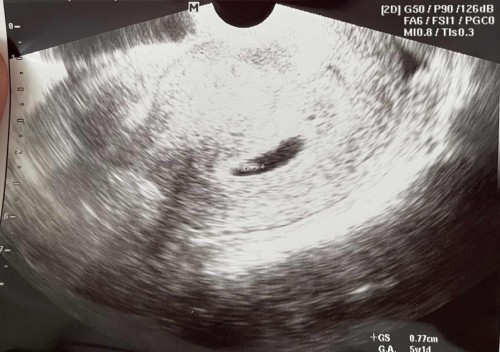

ศุกร์ที่แล้วไปซาวเจอแต่ถุงไข่แดง6week วันนี้ไปซาวเจอตัวน้องแล้วแต่หมอบอก5week ไข่เราตกไปวันที่6กพ. นับตามแอพในนี้แล้วจะ7week แต่ยังไม่เจอหัวใจน้องนะคะหมอไม่ดูหัวใจเพิ่มเพราะคำนวนว่าพึ่งได้5week

น้องยาว 0.77ซม. น่าจะ5-6วีคไหมคะ เพราะของเราไปซาวด์ช่วง7วีค น้องยาว 1 ซม

ในรูปมีบอกนะคะ มุมล่างขวา 5w1d